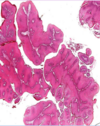

Adenocarcinoma of colon

MALIGNANT TUMOR formed of irregular acini infiltrating the submucosa and muscle layer. Malignant cells vary in size and shape

Red: normal mucosal glands Black: Malignant glands

Malignant